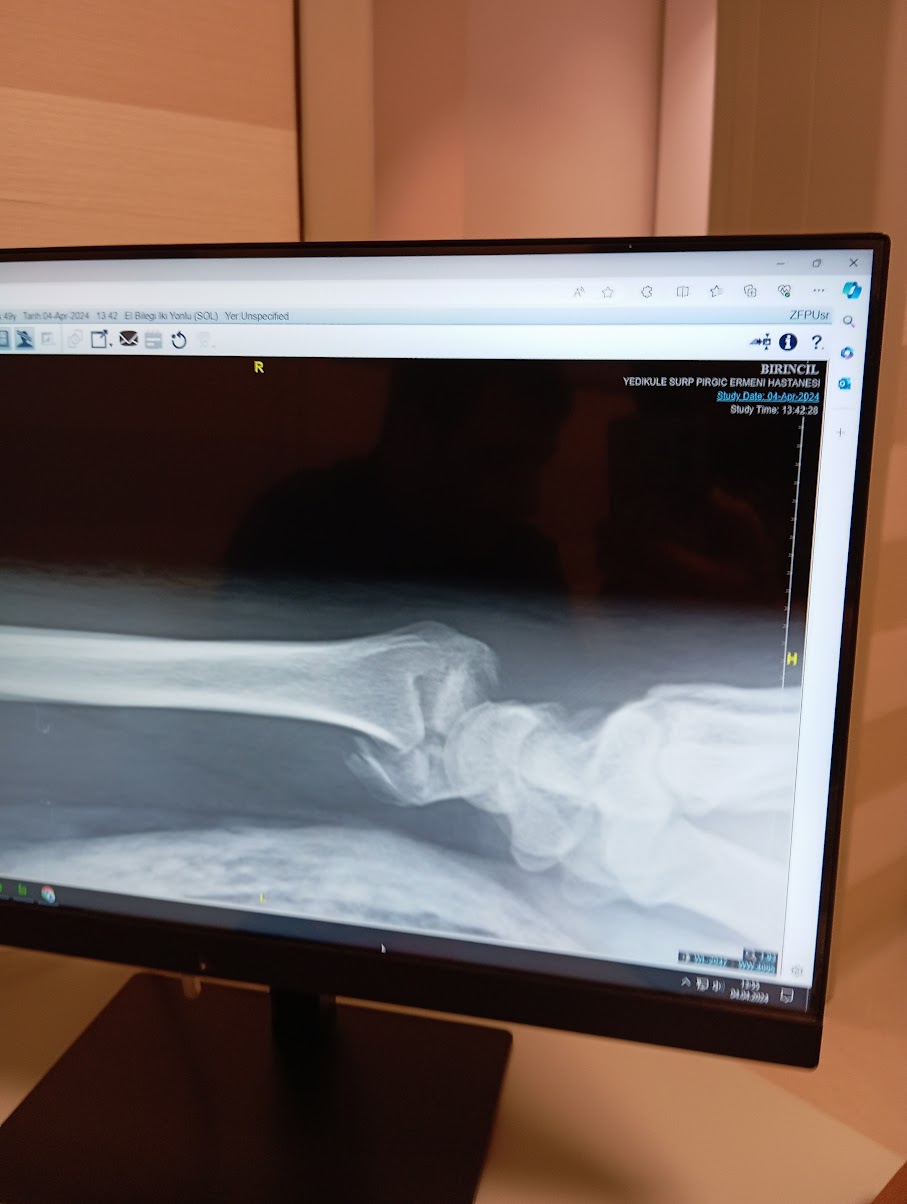

Bugun ikinci gorus almak için Yedikule Surp Pırgiç Ermeni Hastanesine gittik. Doktor ilk rontgene baktıgında, yok ameliyet olman lazım dedi..ama haydi son defa bir rontgen cekelim dedi….gel gor ki AMELİYATA GEREK KALMADI!!!!Bilegimi tekrar oturtular, ve alciya aldilar. Bir ay sonra gene rontgen, akabinde hersey duzgun oturmussa, ciddi bir fizik tedavisiniden sonra yitmis olacagim! Annem ile o kadar sevindik ki…zaten sigortam yoktu…sırf doc muaneye, alcı ve iki rontgen 14k tutmustu ki ameliyat olsaydım…yarağa yering sarabı acardık. Taksim Devlet Hastanesine de sikeyim..ne düzgun oturtular, ne düzgün alcıya aldılar....neyse tüm arkadaslarımın ilgilisi ve sevgisi, ozellikle annem zaven ve emergency room da beni yanlız bırakmayan ablama ve calıstğım sirket Social Thinks in anlayaışı için çok tsk. sizleri seviyorum.

Today we went to Yedikule Surp Pırgiç Armenian Hospital to get a second opinion. When the doctor looked at x-ray that was taken the day of the accident , he said no, you need to have surgery.. but he said let's take one last x-ray….come to see that , THERE WAS NO NEED FOR SURGERY!!!! They reset my wrist and put it in a cast. İn a months time, another x-ray will be taken, and if everything is in order, after serious physical therapy, I will be good to go.! We were so happy with my mother... I didn't have health insurance . The doctor's examination, plaster cast and two x-rays had cost over 14k so if I had the surgery... we would have opened eat my dick wine. Fuck Taksim State Hospital... the way the reset my wrist , how improper they put me in a cast.... Anyway, thank you very much for the care and love of all my friends, especially my mother, Zaven, and my sister, who did not leave me alone in the emergency room, and the understanding of the company I work for, Social Thinks. I love you.